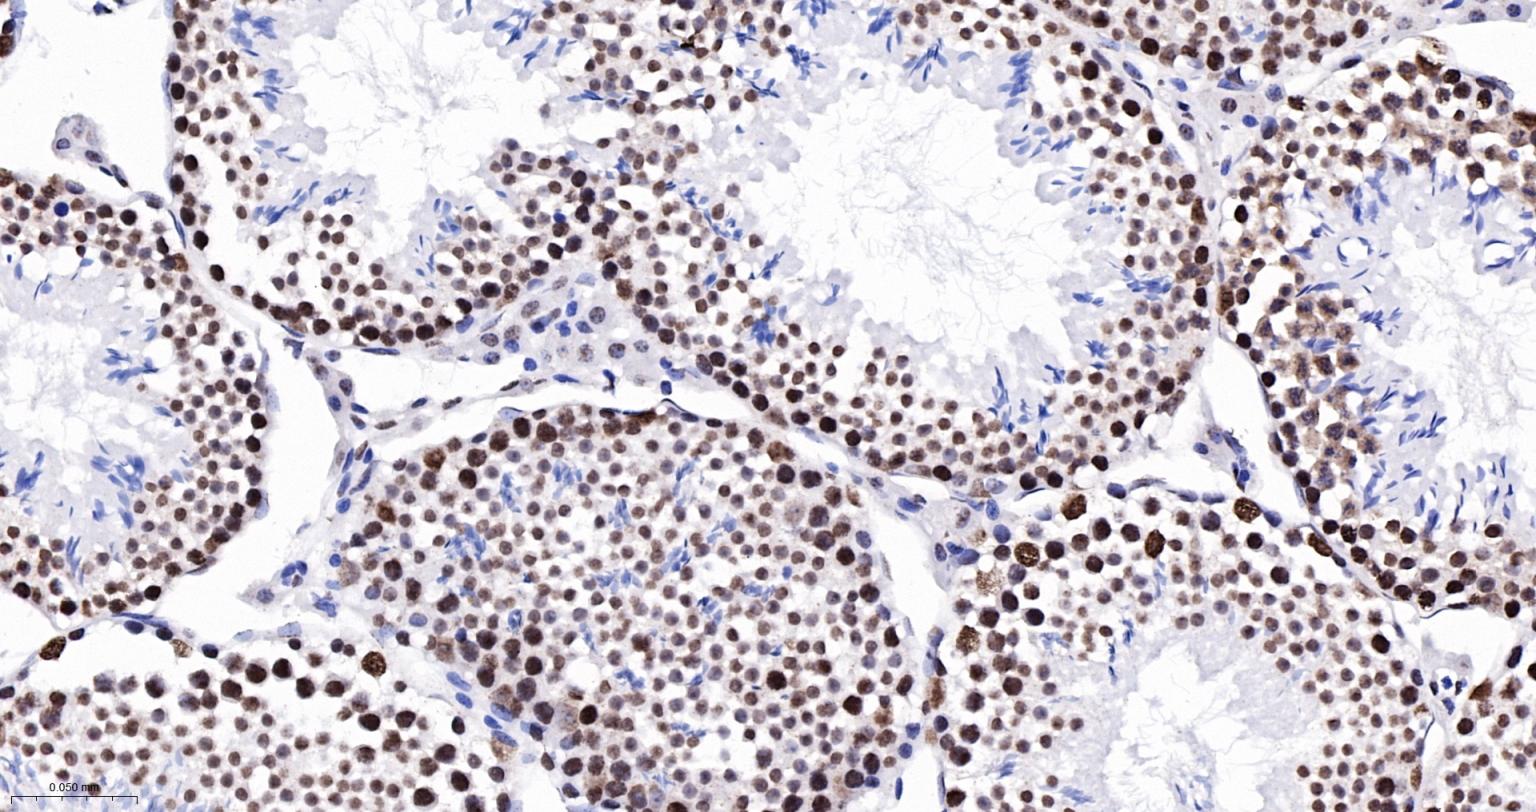

Paraformaldehyde-fixed, paraffin embedded Rat Testicles; Antigen retrieval by boiling in sodium citrate buffer (pH6.0) for 15 min; The section was incubated with SFPQ Monoclonal Antibody, Unconjugated (bsm-61746R) at 1:200 overnight at 4°C, followed by conjugation to the bs-0295G-HRP and DAB (C-0010) staining.